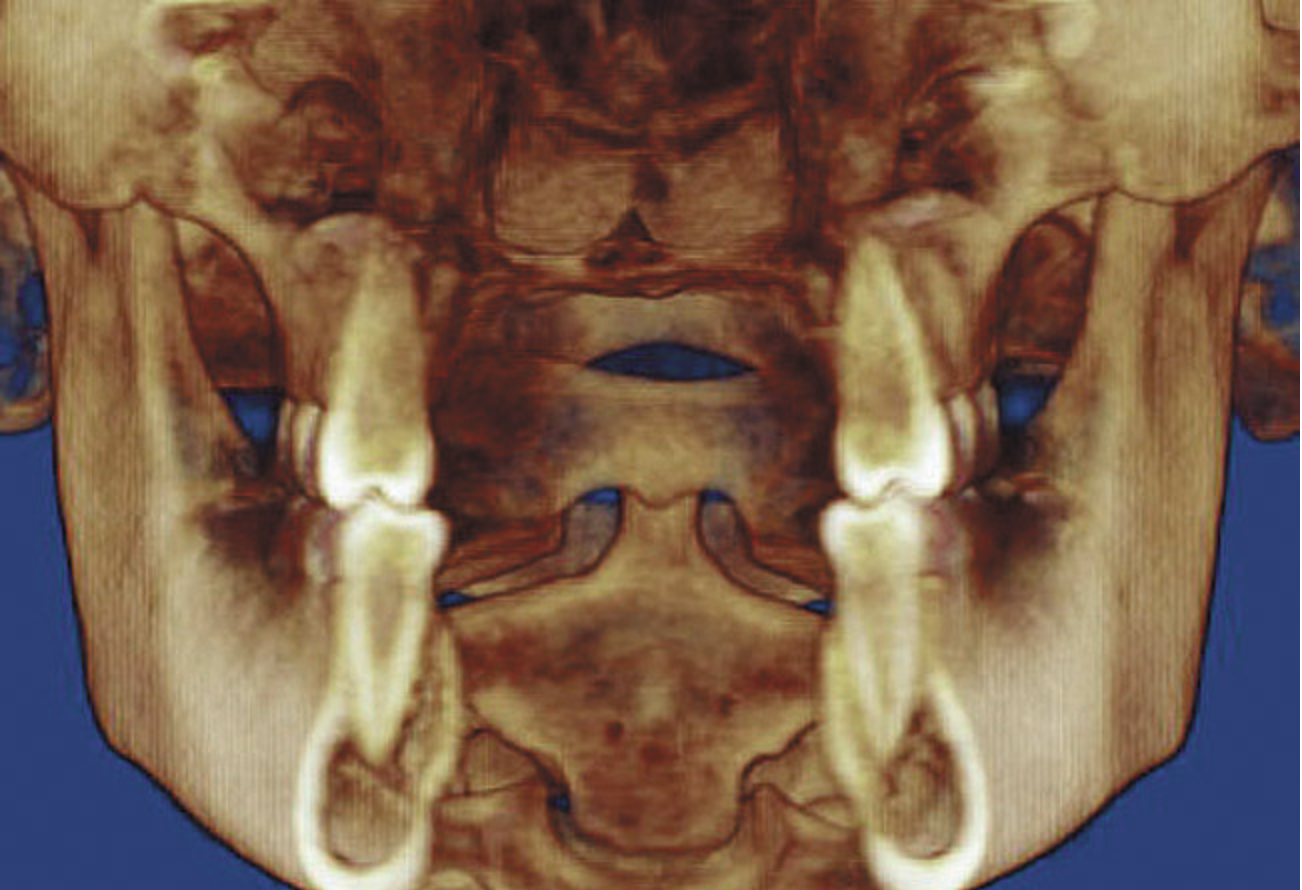

Figure 9A  An example of orthodontic and orthognathic surgery being performed without adequate goals. A) The maxillary central incisors were positioned with severe protrusion. The tooth has been moved through the cortical bone, has forces directed nearly perpendicular to the long axis, and shows evidence of root resorption.

Figure 9A

Figure 9B An example of orthodontic and orthognathic surgery being performed without adequate goals. B) Tomographic evidence of degenerative joint disease and condyles positioned distal to the center of the fossa.

Figure 9B